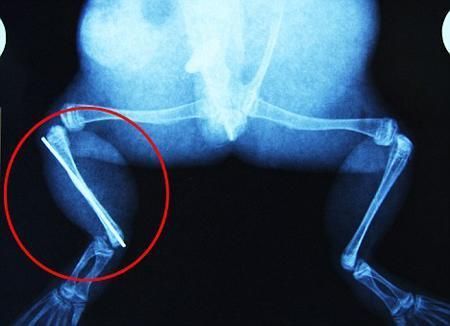

環(huán)球網(wǎng)4月2日報道 據(jù)《每日郵報》報道,上個月,南非大牛蛙布魯萊的右小腿被鄰居家的一只狗咬到,導(dǎo)致粉碎性骨折,現(xiàn)在經(jīng)過2個小時的手術(shù),它的斷腿已經(jīng)被接上,它也因此成為有史以來第一只通過外科手術(shù)用鋼針接上斷腿的青蛙。

野生生物專家安妮經(jīng)常為學(xué)校寫教材,她認(rèn)為這是人類第一次通過手術(shù)給一只青蛙接斷腿。在手術(shù)開始階段,獸醫(yī)把少量給狗用的麻醉藥注入到這只青蛙體內(nèi),讓它失去知覺。然后他在布魯萊的斷腿上切開一個小口,把一根小鋼針植入腿里。最后獸醫(yī)給它縫了9針,把切口縫合在一起。僅僅幾周后,布魯萊就能在安妮家附近活動了。這只青蛙大約已有25歲,主要以嚙齒動物、蛇和其他青蛙為食。布魯萊所屬的牛蛙種群正在不斷減小,目前只能在非洲南部的濕地里才能看到這種青蛙。